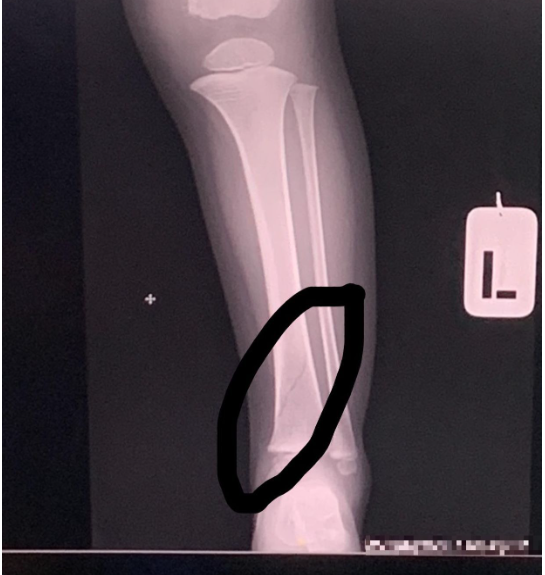

(八打灵再也16日讯)一位父亲控诉新买不到一个月的椅子断裂,造成其孩子摔断左腿,在网上询问网民能否就此事对相关家私店采取法律行动要求赔偿。

“长话短说就是椅子断裂造成我的孩子跌倒,并导致左腿摔断。想要知道我可以投报吗?我能不能对该家私店采取行动?很遗憾造成孩子断腿,(我)想要求赔偿。”

除了质疑伤者有否正确使用椅子外,也有网民质疑若是椅子在好好坐着的情况下发生断裂,那受伤的部位很大可能是臀部或腰部,而非如今的腿部,因此怀疑伤者在事发时的坐姿和使用方式。